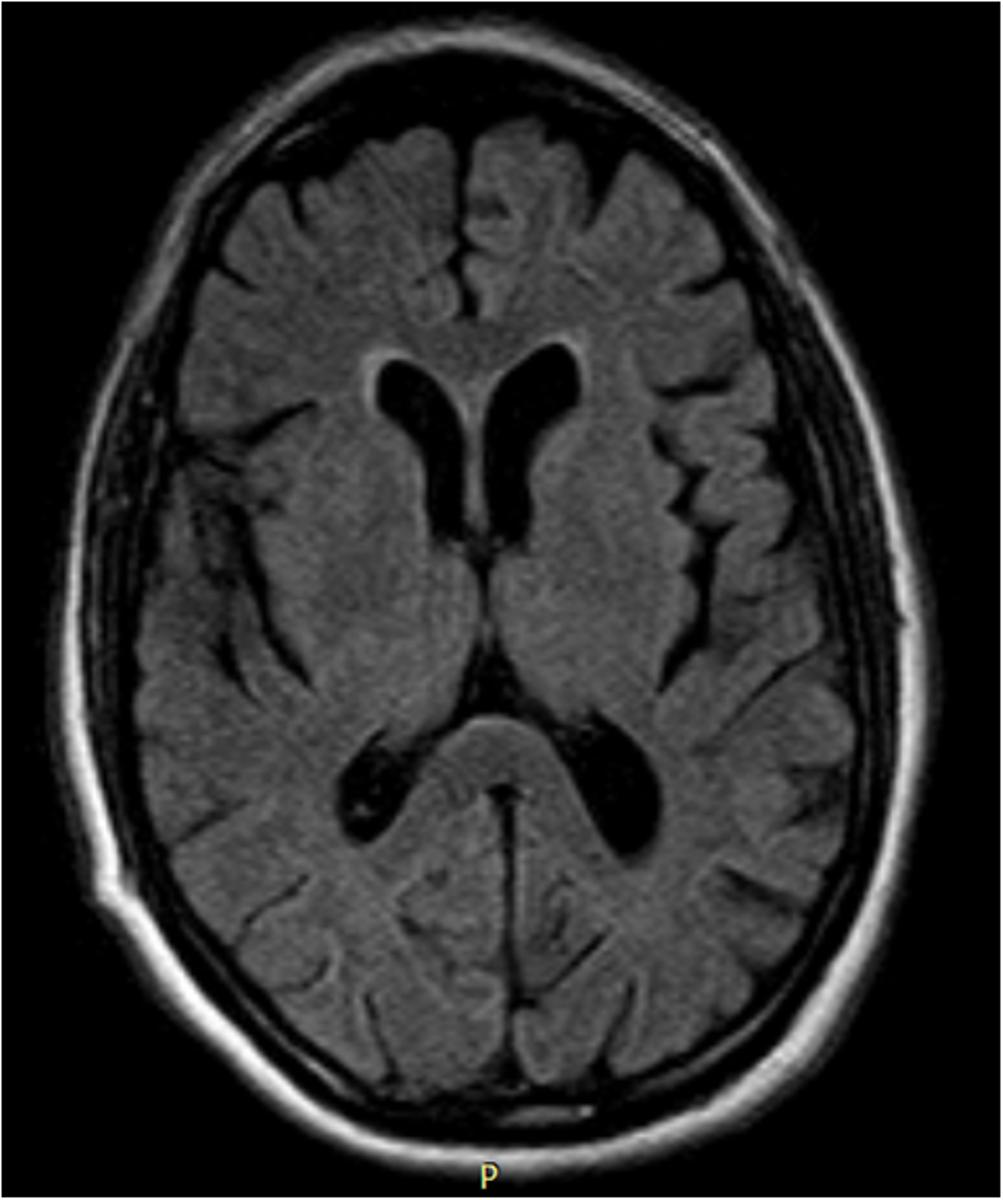

Background: Catatonia is a neuropsychiatric syndrome, classically related to schizophrenia, but more often associated with other psychiatric, neurological and/or metabolic causes.Case Report: A 61-year-old man was admitted in the Psychiatric Department with catatonia of unknown etiology. He was submitted to a detailed investigation including electroencephalogram that revealed triphasic periodic activity and cranial magnetic resonance imaging that revealed brain cortical and subcortical atrophy of frontal and medial temporal predominance. The patient was then transferred to the Neurology Department. An increase of 14.3.3 protein in the cerebrospinal fluid, was detected and a presumptive diagnosis of spongiform encephalopathy was made. The clinical picture worsened with plurisegmental myoclonus, episodes of ocular deviation and dystonia. The patient died after 5 weeks. Anatomopathological examination confirmed the diagnosis of sporadic Creutzfeldt-Jakob disease.